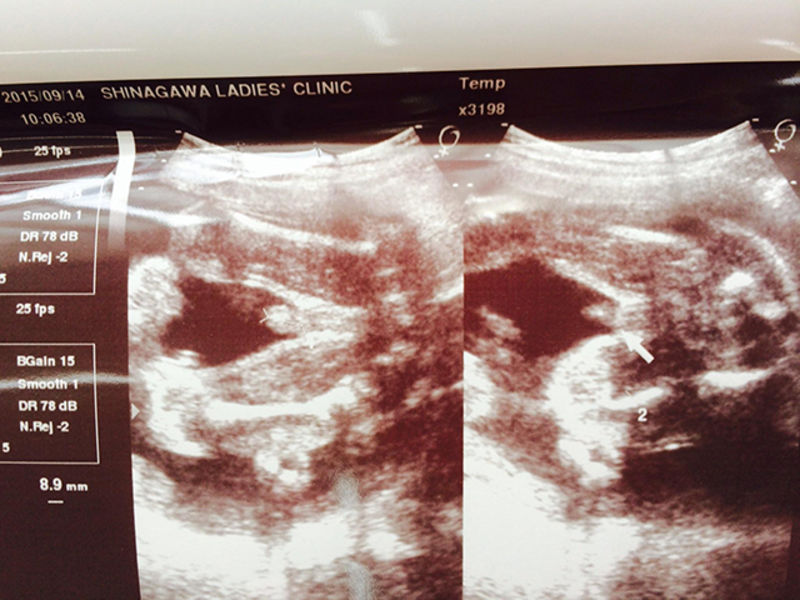

妊娠6ヶ月 胎児の成長 妊娠生活book